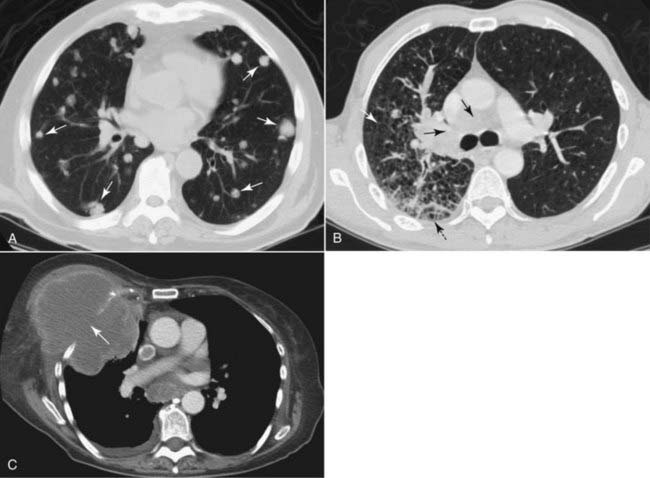

image

Figure 3-15 Metastases to the lung, CT scans.

A, Multiple discrete nodules of varying size are present throughout both lungs (solid white arrows). The diagnosis of exclusion, whenever multiple nodules are found in the lungs, is metastatic disease. In this case, the metastases were from colon carcinoma. B, The interstitial markings in the right lung are prominent (solid white arrow), there are septal lines (dotted black arrow) and lymphadenopathy (solid black arrows) from lymphangitic spread of a bronchogenic carcinoma. C, In this case, the lung cancer has grown through the chest wall (solid white arrow) and invaded it by direct extension. The pleura usually serves as a strong barrier to the direct spread of tumor.